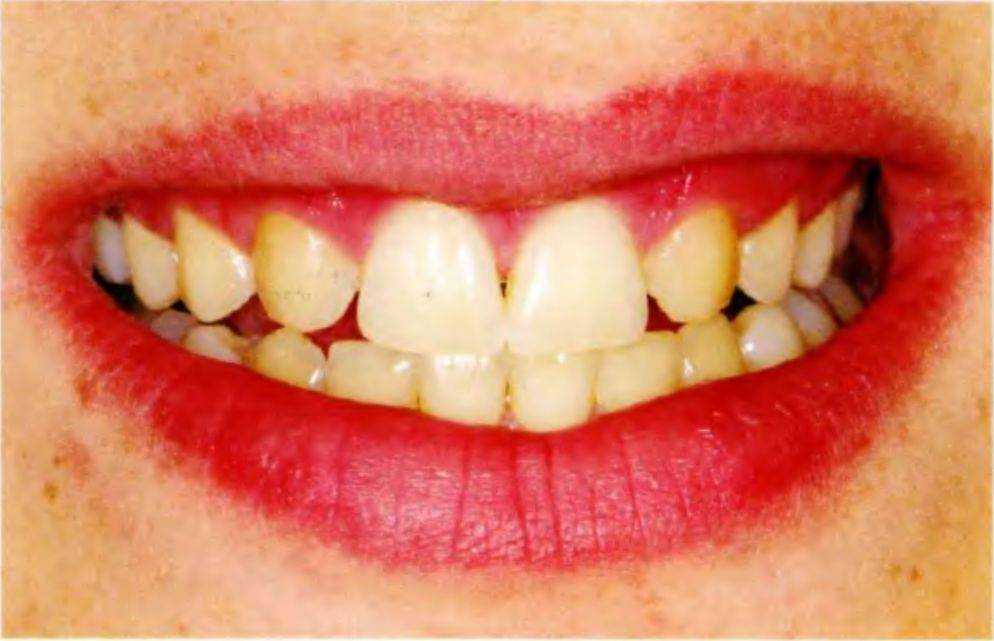

Рис. 5-За. Тринадцатилетний пациент с врожденным отсутствием боковых резцов верхней челюсти с помощью ортодонтических методов и последующее протезирование позволяют получить эстетически и функционально благоприятный долгосрочный результат. Таким образом достигается естественное положение клыков, оптимальное как с функциональной, так и с эстетической точки зрения. Только в нем они способны выполнять направляющую функцию при боковых и протрузионных движениях нижней челюсти. К передней группе зубов относится только медиальная часть клыка, дистальная часть относится к дистальной группе (рис. 5-2).

Рис. 5-Зс. Линия улыбки пациента